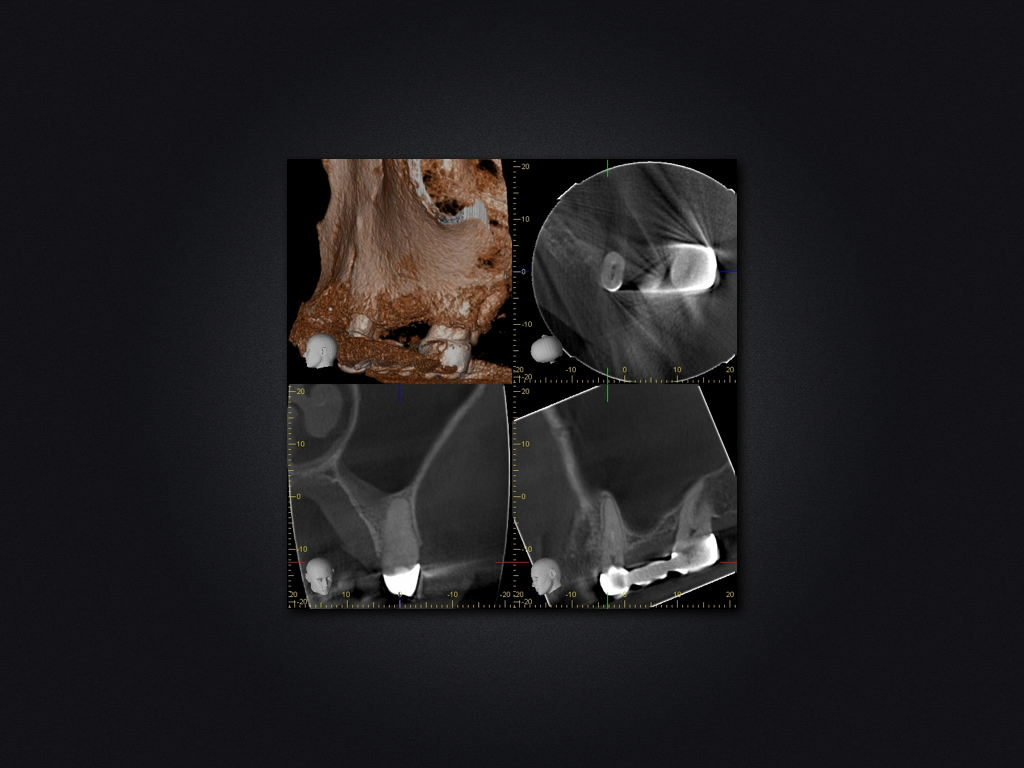

25D.002

Spülzwischenfall?